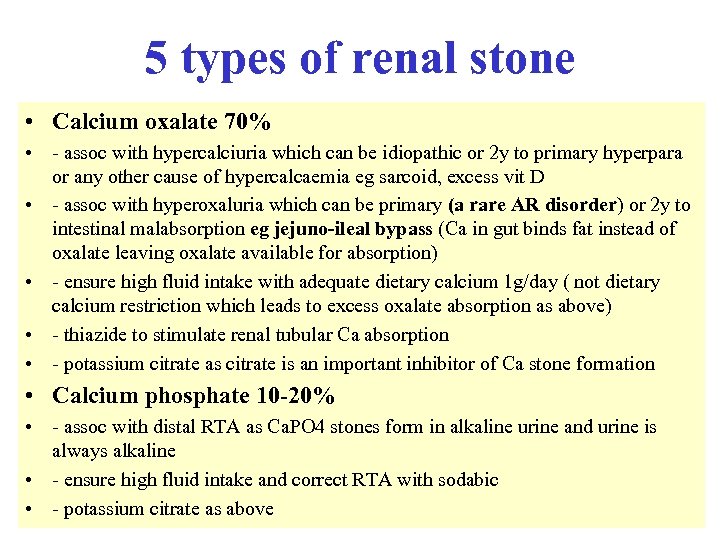

Reduced serum complement • • Occurs in: - SLE - infective endocarditis - post strep nephritis - shunt nephritis - cholesterol embolism - cryoglobulinaemia - MCGN types 1 and 2 • • Complement normal in FSGS, amyloidosis, Alports, anti GBM disease C 3 nephritic factor is an Ig. G auto antibody to the C 3 convertase of the alternative pathway of complement activation, found in both types of MCGN